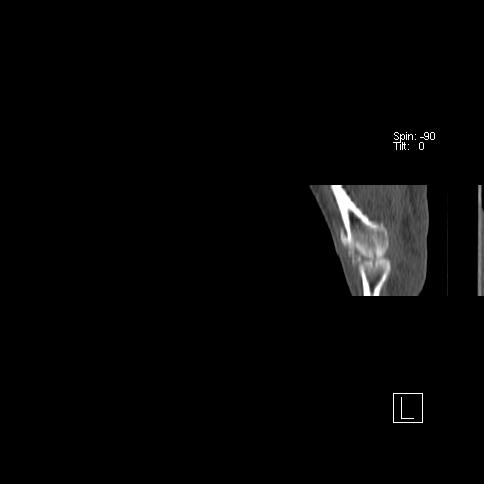

标题: CT13415:M72Y,跖趾关节病变,请会诊 [打印本页]

标题: CT13415:M72Y,跖趾关节病变,请会诊

男72岁左侧跖趾关节肿痛15年,查压痛。

考虑退行性骨关节病。